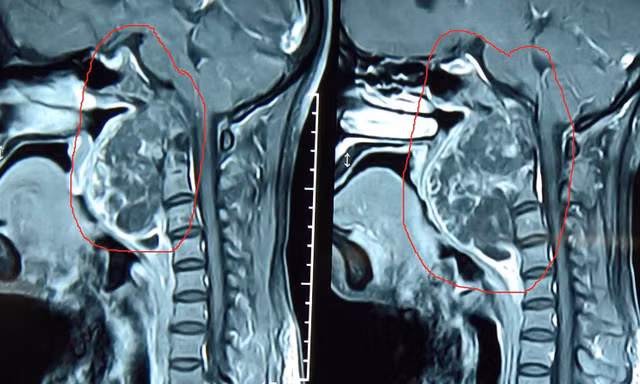

TPO - Bệnh nhân bị u nguyên sống, một bệnh lý ác tính do tế bào “còn sót lại” trong bào thai. Khối u nằm ở vị trí cực "hiểm" , “vắt” từ nền sọ xuống cột sống và“nuốt trọn” động mạch cảnh trong.